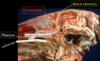

Anatomie de la poche gutturale

A

Diverticule de la trompe d’eustache

- vaisseaux importants

- nerfs importants

- passage d’air à l’intérieur de la poche

- os styloide qui coupe la poche en 2 (medial et latéral)